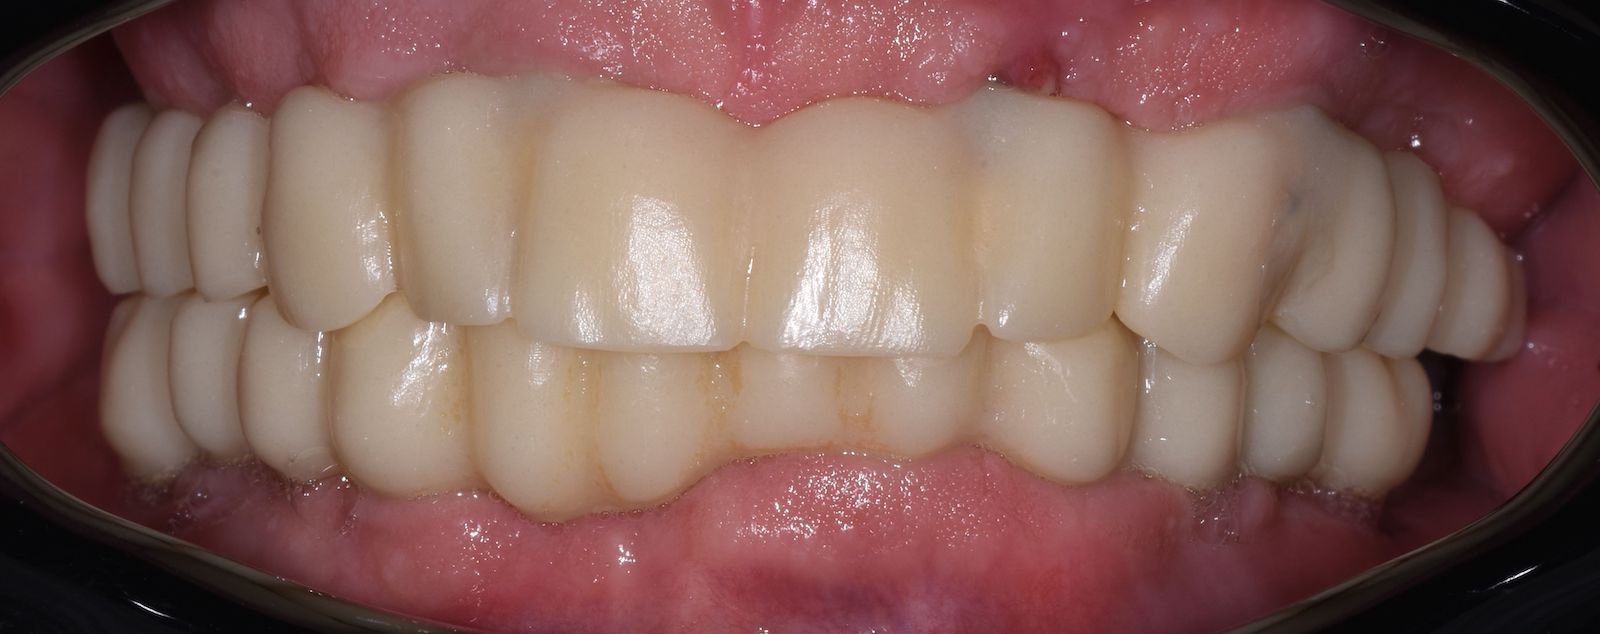

3. Odevzdání hotové zubní náhrady.

Po odsouhlasení přesného dosedu, správného tvaru a skusu zhotovujeme definitivní zubní náhradu 👇